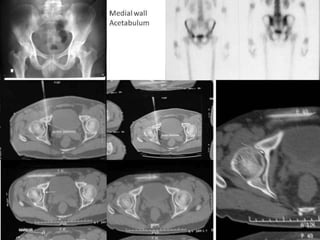

Osteoid Osteoma - CT

• CT is more accurate than MRI.

• CT helped in confirming the diagnosis of

osteoid osteoma in 74% of cases.

• Szendroi et al reported accuracies of about

66% in the diagnosis of intra-articular lesions

and 90% in extra-articular lesions.

• To date, CT scanning is the primary

investigational tool for the definitive diagnosis

of osteoid osteoma.

Osteoid Osteoma – Bone scan

• To date, no negative bone-scan findings have

been reported in patients with osteoid

osteoma.

• Bone scanning is currently the most accurate

means of localizing the tumour.

• Wells et al noted that the sensitivity of

skeletal bone scan for osteoid osteoma is

100%.

• A bone scan is helpful in

detecting the "doubledensity sign," which is a

focal area of increased

activity with a second

smaller area of

increased uptake

superimposed on it, is

said to be diagnostic of

osteoid osteoma.

• A CT guided needle was passed to localize the

lesion.

• Through an anterior "Hernia" approach the

lesion was approached and excised.

• The Follow-up CT Scanning done to reveal

complete removal of lesion.

• A biopsy confirmed it later.

Osteoid Osteoma -CT • CT is more accurate than MRI. • CT helped in confirming the diagnosis of osteoid osteoma in 74% of cases. • Szendroi et al reported accuracies of about 66% in the diagnosis of intra-articular lesions and 90% in extra-articular lesions. • To date, CT scanning is the primary investigational tool for the definitive diagnosis of osteoid osteoma.

Osteoid Osteoma –Bone scan • To date, no negative bone-scan findings have been reported in patients with osteoid osteoma. • Bone scanning is currently the most accurate means of localizing the tumour. • Wells et al noted that the sensitivity of skeletal bone scan for osteoid osteoma is 100%.

Osteoid Osteoma –Bone scan • A bone scan is helpful in detecting the "doubledensity sign," which is a focal area of increased activity with a second smaller area of increased uptake superimposed on it, is said to be diagnostic of osteoid osteoma.

• A CTguided needle was passed to localize the lesion. • Through an anterior "Hernia" approach the lesion was approached and excised. • The Follow-up CT Scanning done to reveal complete removal of lesion. • A biopsy confirmed it later.